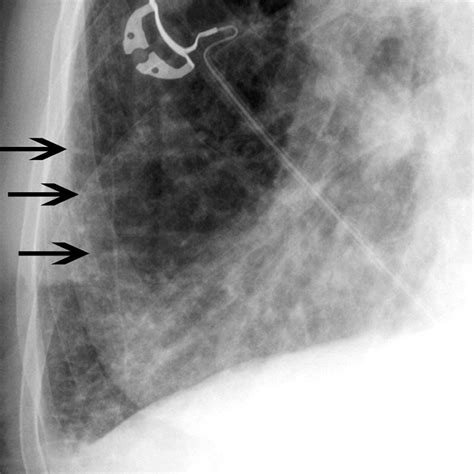

Developing the eye to detect Kerley B lines requires careful inspection of the lung fields, particularly in the costophrenic angles. Because these lines are very thin, they can be easily missed if the image quality is poor or if the exposure is not optimized.

When reviewing a film, look specifically for lines that:

1. Extend all the way to the lateral pleural surface.

2. Are located perpendicular to the pleural line.

3. Do not branch or intersect with other vessels (differentiating them from normal pulmonary vasculature).